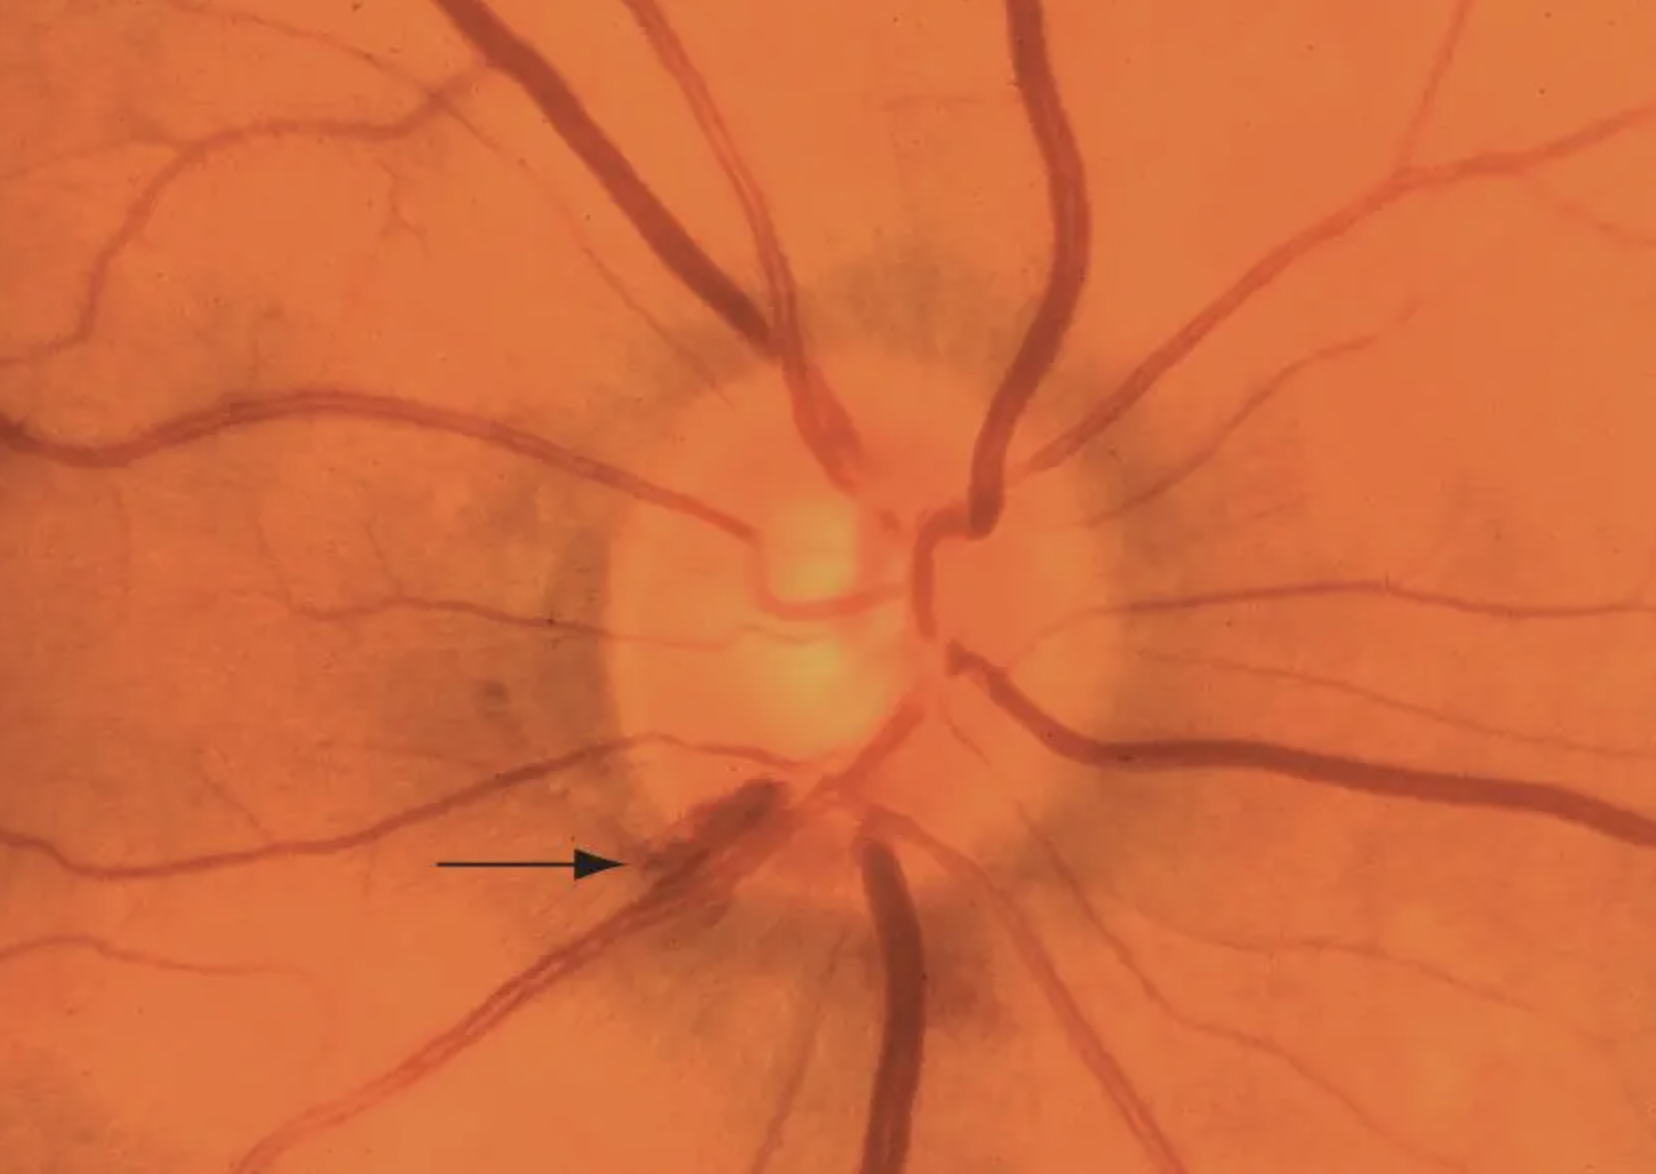

• Baring of circumlinear vessels occurs when rim loss leaves vessels hanging like a rope suspended over a canyon; can also be a nonspecific finding

• Nerve fiber layer hemorrhages (Drance hemorrhages, splinter hemorrhages) on the disc can be highly variable and difficult to spot, even on a dilated exam. Disc photos are much better at picking these up. They occur in about a third of glaucoma patients and remain for weeks to months, followed by localized notching and visual field loss. Disc hemorrhages are more common in normal tension glaucoma and less common in advanced glaucoma (perhaps due to extensive RNFL loss). Disc hemes need to be taken seriously because they signify higher risk for functional vision loss. Very rarely PVDs, diabetes, BRVOs, anemia and blood thinners can also be responsible for optic nerve head hemorrhages.